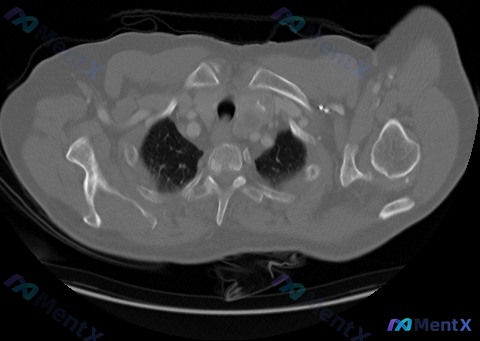

最近看到一份胸部CT纵隔窗的影像资料,整理了一下影像表现和分析思路,和大家分享讨论。 先看影像核心表现 这份图像是胸廓入口及上纵隔区域(主动脉弓上方层面)的横断面: 1. 纵隔结构与淋巴结:气管居中、通畅,气管前及左侧间隙(2R/2L/3区)可见多发软组织密度结节,部分有融合成团趋势,密度相对均匀,...

看到一份资料,觉得挺有讨论价值的,整理一下思路和大家分享。 --- 先把看到的信息捋一下 核心「矛盾点」(或者说关注点) 输入主诉/关键特征:明确提到是 「双侧对称性肺门及纵隔淋巴结肿大」。 影像描述重点:胸部增强CT(纵隔窗)主要描述了 左侧肺门及隆突下(7区、10区)的融合性软组织团块,有占位效...